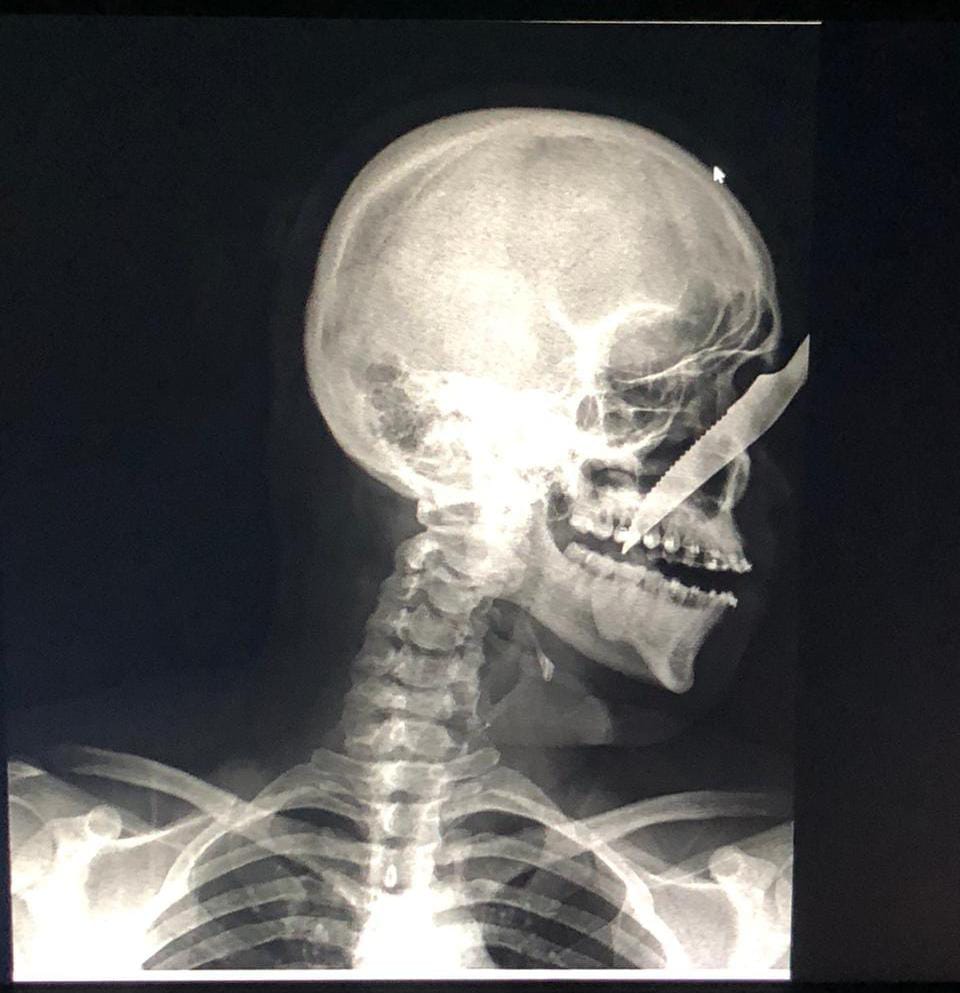

Alberto Carvalho de Oliveira, de 25 anos, recebeu uma facada no rosto que ficou cravada no nariz de um homem identificado como sendo André Luís Benevides Carvalho, de 35 anos. O caso ocorreu na última sexta-feira (17), no município de Carauari, interior do Amazonas.

A vítima passou por cirurgia onde retirou a faca e não corre risco de morte.